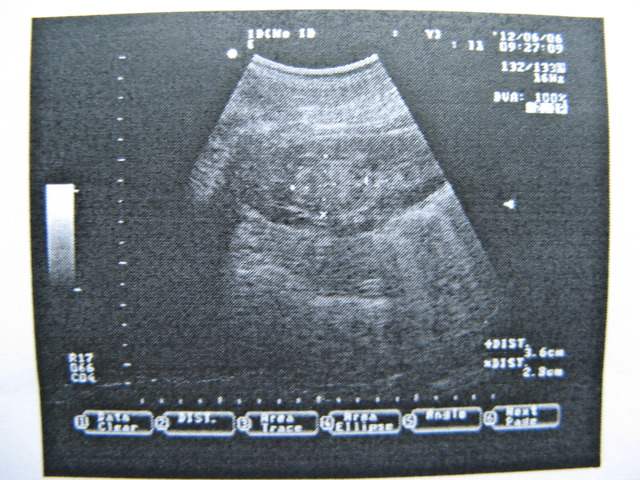

CT资料:

img